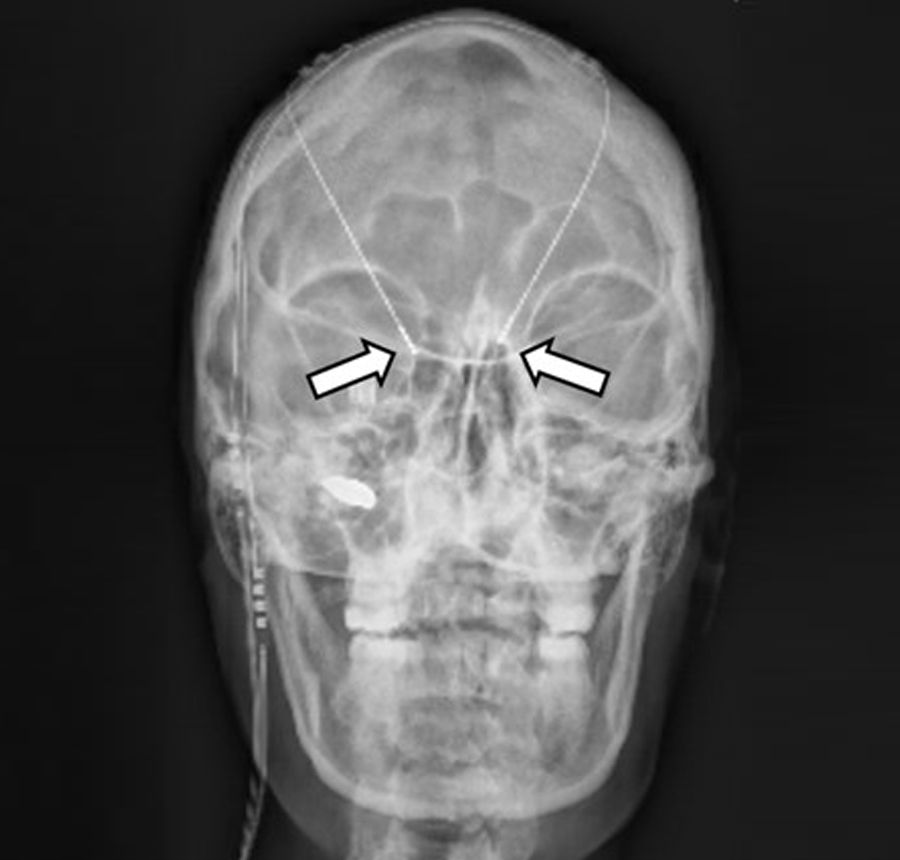

Bei der Tiefen Hirnstimulation (engl. Deep Brain Stimulation, DBS) werden feine Elektroden gezielt in bestimmte Hirnregionen eingesetzt. Durch einen Impulsgeber und elektrische Impulse über die Elektrode können überaktive oder fehlgesteuerte Nervenzellen moduliert werden, um Symptome wie beispielsweise ein Zittern oder Muskelsteifigkeit zu lindern. Die Tiefe Hirnstimulation wird hierbei zur Behandlung von Bewegungsstörungen wie Morbus Parkinson oder Essentiellem Tremor sowie auch bei schwer behandelbaren Epilepsien eingesetzt.

Die Implantation der Elektroden erfolgt hierbei mittels rahmen-basierter, rahmen-loser und roboter-assistierter Verfahren.